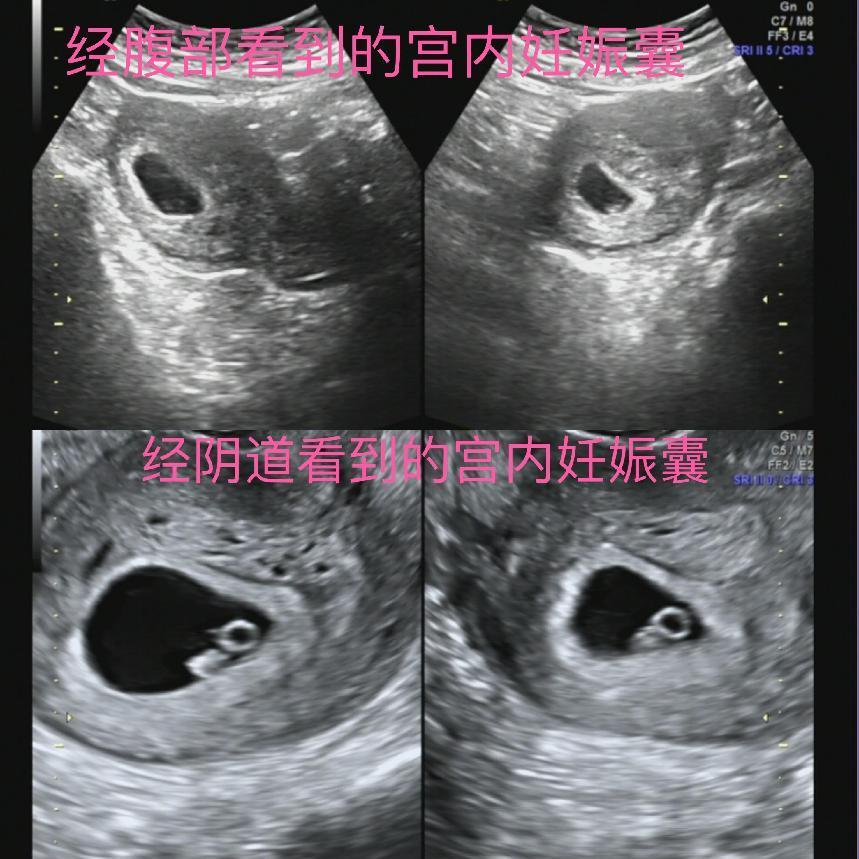

可以。在孕早期进行阴道超声检查,并不会影响到胎儿的生长发育情况。目前没有研究证据显示阴超对胎儿有害,国外现在基本上第一次做产检,都是做的阴超。宝妈们不用过于焦虑,当然如果无法克服心理障碍,一般的早孕检查做腹部B超也是可以的,但是如果怀疑有宫外孕或其他病症,就要听医生的做阴超。

1. 经腹部超声检查:有、无性生活都可以进行检查,检查前需要充盈膀胱,也就是常说的“需憋尿”。

2. 经阴道超声检查:有性生活史者才可以进行检查,无需充盈膀胱,且检查前需要把尿排空,否则会影响检查。